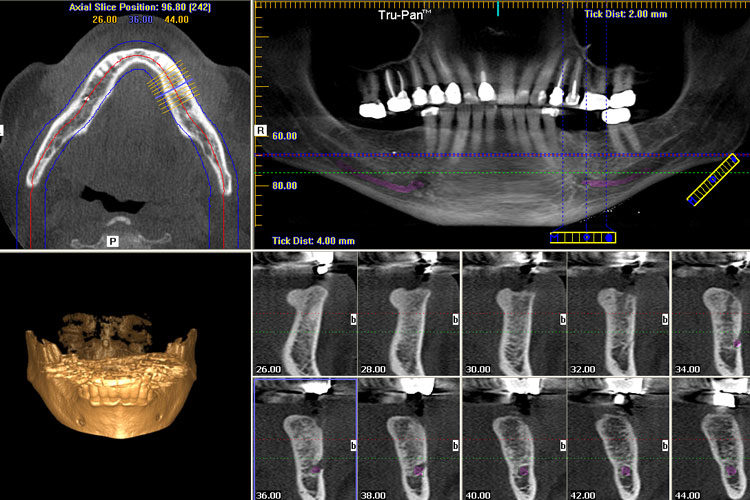

3D Diş Tomografisi, konik ışınlı bilgisayarlı tomografi (CBCT) teknolojisi kullanılarak dişlerin, çene kemiklerinin ve çevre dokuların yüksek çözünürlüklü üç boyutlu görüntülerini elde etmeyi sağlayan bir yöntemdir. Bu teknoloji, geleneksel iki boyutlu röntgenlere kıyasla daha ayrıntılı ve katmanlı görüntüler sunarak tanı ve tedavi süreçlerini iyileştirir.

İmplant Planlaması: Çene kemiğinin yapısı ve yoğunluğu değerlendirilerek implant yerleştirme süreci optimize edilir.

- Gömülü Dişlerin Tespiti: Özellikle 20 yaş dişlerinin konumu ve çevre dokularla ilişkisi belirlenir.

- Kist ve Tümör Teşhisi: Patolojik oluşumların boyutu ve yayılımı hakkında detaylı bilgi sağlar.

- Kanal Tedavisi Öncesi İnceleme: Kök kanallarının yapısı ve olası komplikasyonlar değerlendirilir.

- Ortodontik Tedavi Planlaması: Dişlerin ve çene kemiklerinin konumu analiz edilerek tedavi süreci planlanır.

Üç Boyutlu Görüntüleme: Diş ve çene yapılarının detaylı 3D görüntüleri elde edilir.

- Yüksek Çözünürlük: Kemik ve yumuşak dokuların net görüntülenmesi sağlanır.